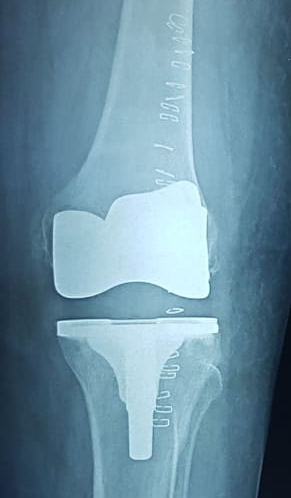

PROFILE TRAINING AND PRESENTATION Dr. Niranjanan Recieving Diploma SICOT degree in Rome, Italy Dr. Niranjanan being awarded fellowship certificate at Indian spinal injuries centre CLIINIC SOME OF Dr. NIRANJANAN's CASES